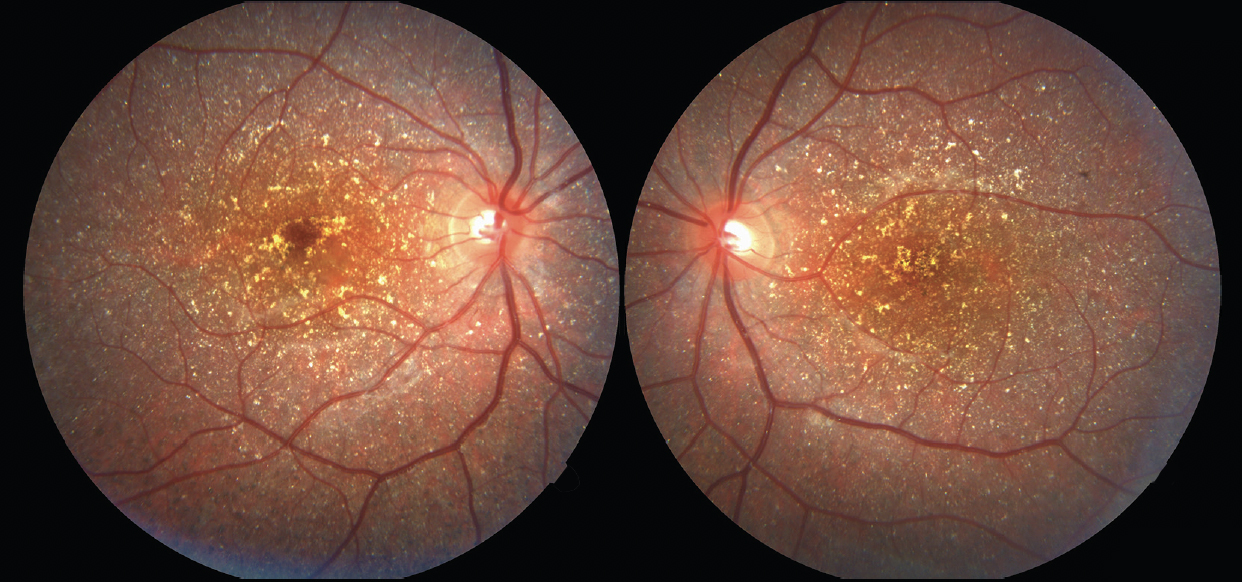

Дослідження переднього сегмента кожного ока не було значимим. Кольорова фотографія очного дна виявила дифузні блискучі жовто-білі кристалічні відкладення на задньому полюсі сітківки кожного ока (рис. 1). Автофлуоресценція очного дна (FAF) також показала гіперфлуоресцентні відкладення на задньому полюсі кожного ока (рис. 2)

Рисунок 1.